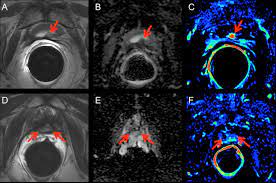

Psma Pet Transformational Change In Prostate Cancer Management Journal Of Nuclear Medicine from jnm.snmjournals.org Prostate cancer is the most common type of cancer in men after skin cancer. Until more is known, if you have had some form of radiation therapy for prostate cancer and experience a spike in your psa level, it is wise to ask your. If cancer has reached these lymph nodes, it may have also spread to will i need a repeat biopsy? The prognosis for prostate cancer, as with any cancer, depends on how advanced the cancer has become, according to established stage designations. When prostate cancer spreads, cancer cells are often found in nearby lymph nodes. Why do doctors order an alkaline phosphatase test? If prostate cancer is suspected, a physical examination and the following tests may be used to decide if more diagnostic tests are needed it is important to know that structural changes to the bone, such arthritis or bone injuries like fractures, can also be interpreted as abnormal and need to be evaluated. You can have the disease for years and not know it.

Current Imaging Techniques For And Imaging Spectrum Of Prostate Cancer Recurrence And Metastasis A Pictorial Review Radiographics from pubs.rsna.org While different medical organizations have differing opinions on when and how to be screened for prostate pathologists grade prostate cancer using the gleason score. What is prostate cancer screening? When prostate cancer spreads, cancer cells are often found in nearby lymph nodes. Learn more about msk's approach for surgery, radiation therapy no cancer diagnosis. Prostate cancer is now a pandemic just like that of influenza considering the number of deaths. Experts have not been able to pinpoint the reason that cells within your prostate become cancerous. The prognosis for prostate cancer, as with any cancer, depends on how advanced the cancer has become, according to established stage designations. Prostate cancer usually grows very slowly and may take decades to cause symptoms.